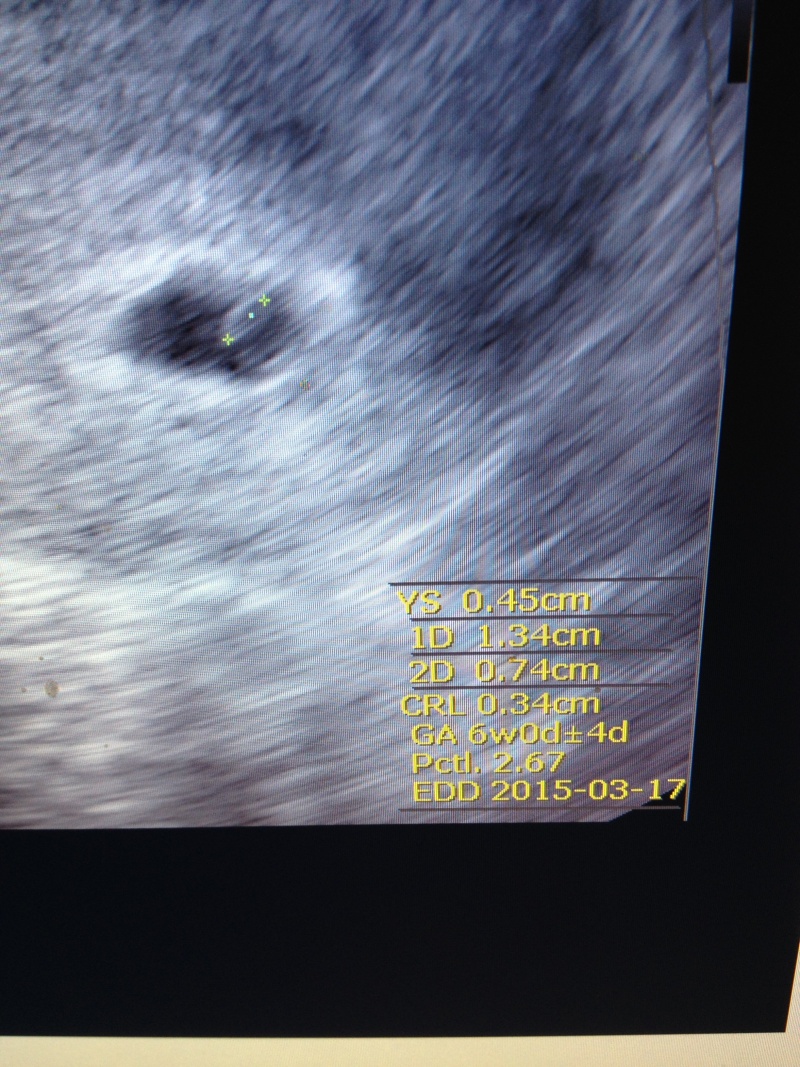

Most megvárjuk a szívhangot (bár ha addig véletlenül lehányok valakit, akkor nem várunk addig

) aztán elmondjuk, bár szerintem anyum már vágja.. célozgatott is rá, meg mindig a hasamat lesi.